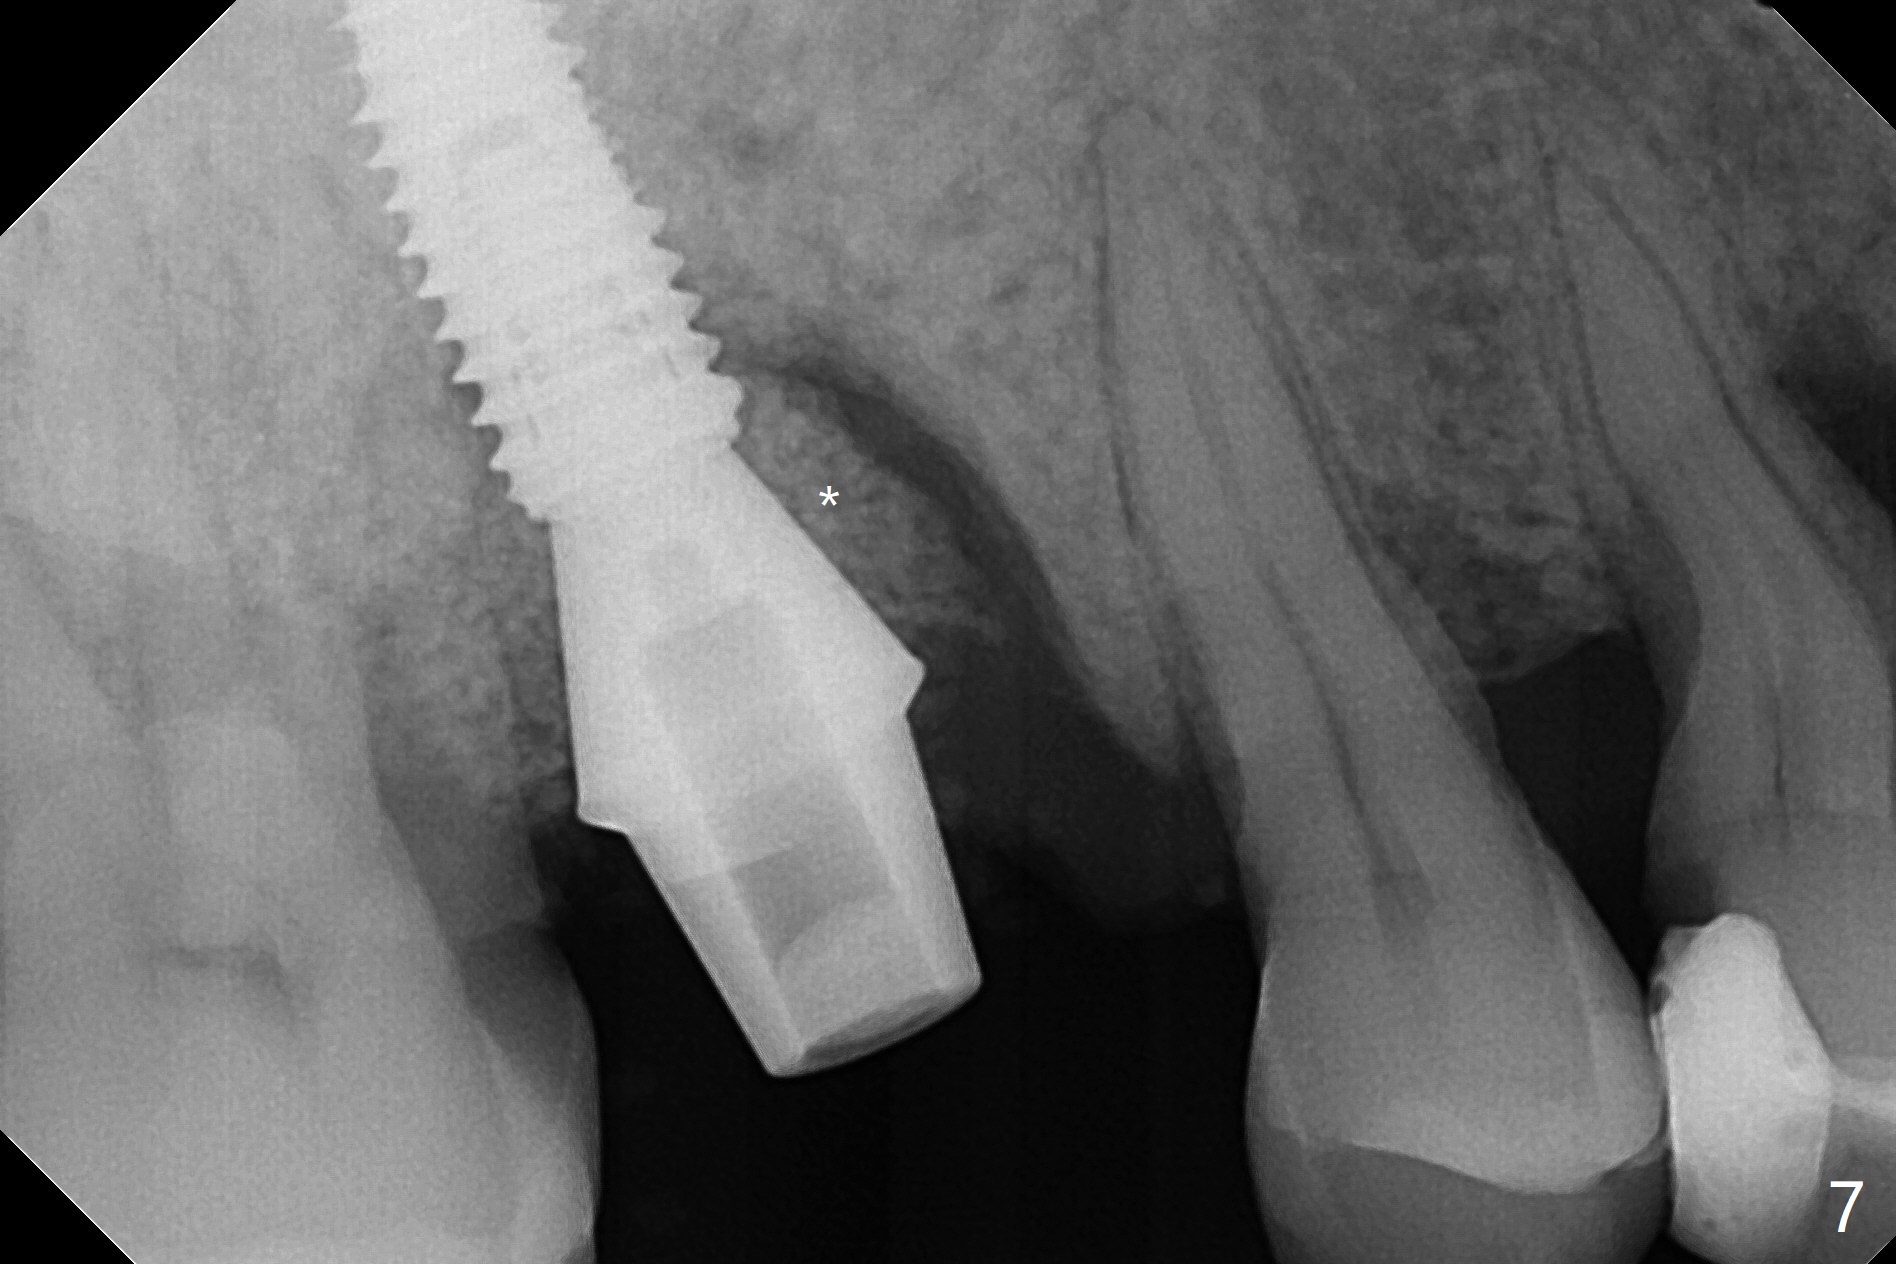

53岁男吸烟,牙周炎,咬合力大,3号牙颊侧(图一),腭侧(图二:P)牙龈退缩,尤其是近中颊侧根(图一:MB),拔牙后,中隔冠方(表面)有好像健康的牙龈(图三:*),近中,远中连接处切开(图三:虚线),将中隔牙龈推向近中颊侧牙槽窝(图四:箭头),修复退缩牙龈,而且暴露下面中隔(S),接着在它上面导板钻洞,避免软组织创伤。利用报废植体试图内提升(图五(红虚线:窦底)),最终正式植体完成提升(图六:黑*),初步在牙槽窝深部放置粘性骨粉(白*)后,放入基台,之后再次在植体,基台周围放置骨粉(图七:*),最后借助临时牙冠(图八,九:T)和外衬里(图八:R)封闭牙槽窝开口,G是近中颊侧迁移的牙龈。植体垂直进入上颌窦可以减少窦膜破裂(图五,六,九),术后没有鼻出血。术后1个月临时牙冠松动,去除牙冠和基台,安置愈合帽(图十)。表面骨粉遗失,但是颊侧移位的中隔牙龈好像帮助软组织预后。